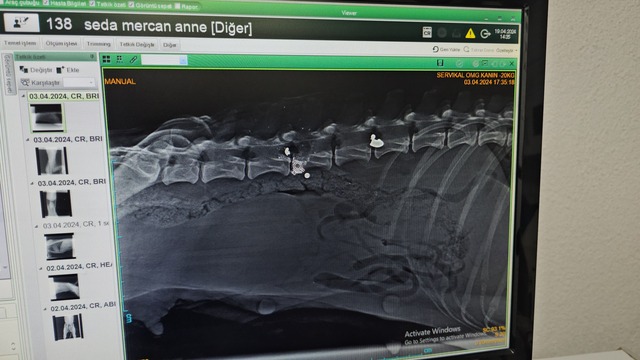

Köpeğin yaralı, yavrularının ise yeni doğmuş olarak geldiğini söyleyen veteriner hekim Ömer Faruk Alkan, "Röntgeni çekip muayene ettikten sonra yakın mesafeden ateş edildiğini, saçmaların omuriliğin içine ve vücuduna saplandığını gördük." dedi.

Omurilikteki saçmayı arka tarafı felç kalacağı için bulup çıkarttıklarını kaydeden Alkan, "Omuriliğin etrafındaki kemik dokusunu serbestleştirerek oradaki sinirin baskısından kurtardık. Sonra yavrularının yanına koyduk. Bir hafta kadar fizik tedavi uyguladık ama 1 ayakta felç olduğunu gördük. Hiç his yoktu. O ayak ve kuyruğu ampute ettik. Diğer ayakta da fizik tedavisi sürüyor. Fizik tedavide lazer ve yürütme egzersizleri yapıyoruz. Şu an ilk geldiğine göre çok iyi ama uzun süre tedavi görmesi gerekecek. Yavruların durumu çok iyi sadece 1 tanesini kaybettik. O da aldığı silah yarasından olabilir. Yavrular bize yeni doğmuş şekilde geldi" dedi.